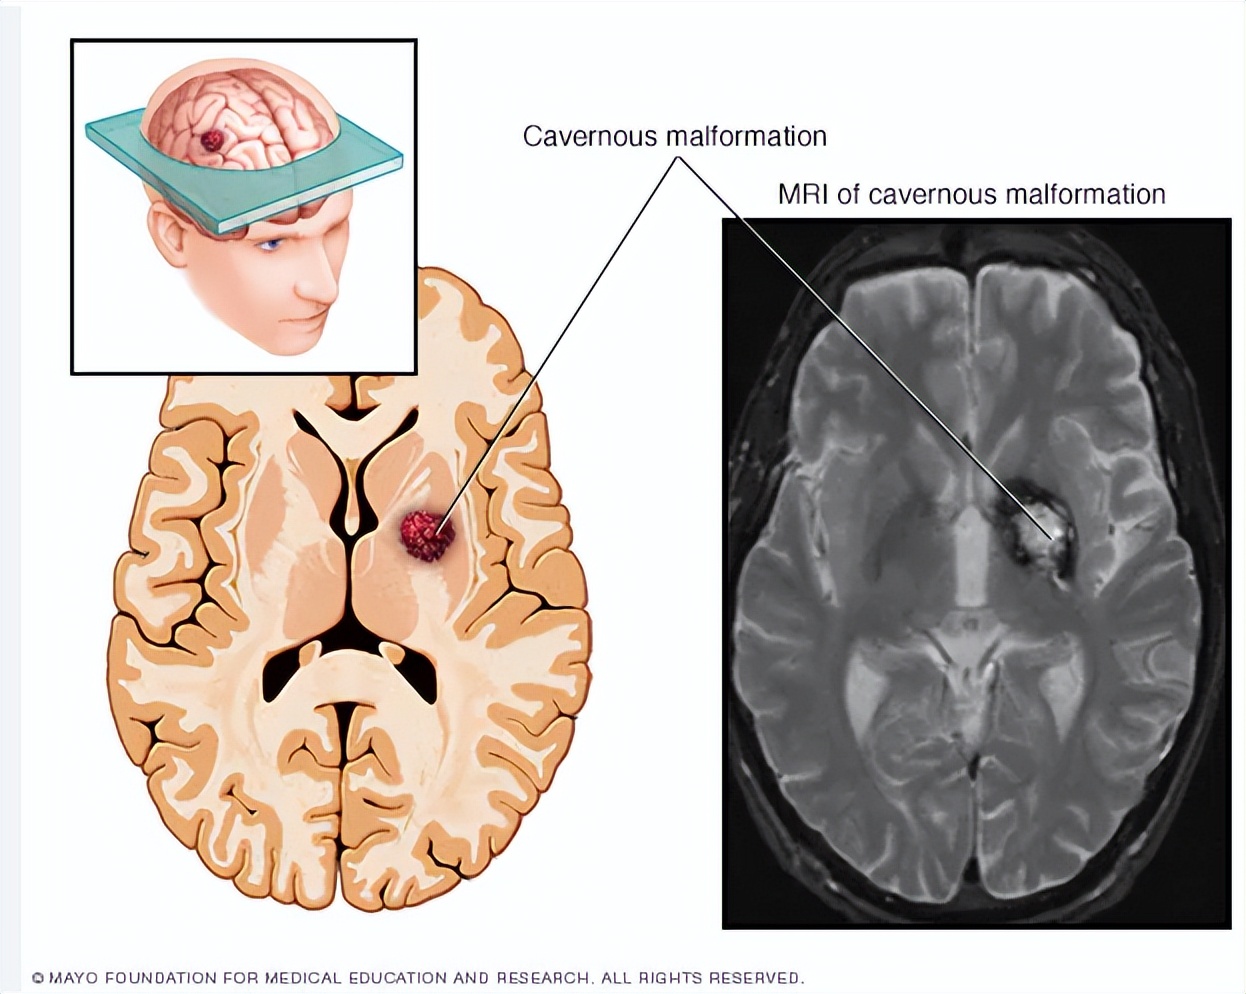

脑海绵状血管瘤的 诊断要通过头颅CT或MR影像手段来确定,影像学上有点像“ 爆米花 ”或“ 桑椹 ”样(血管壁非常薄),影像特点与反复出血后周围组织有较多含铁黄素沉积相关。如果考虑到可能患有该疾病,应尽早进行影像检查,其中磁敏感SWI成像是最具诊断价值的方法。